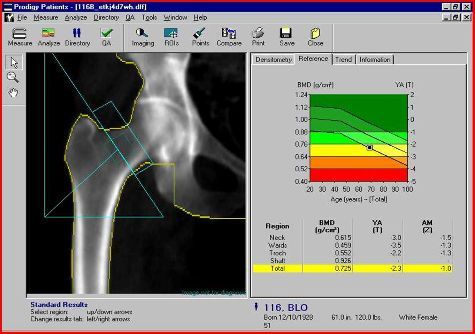

La MOC (Mineralometria Ossea Computerizzata). Questa è una metodica da molti sottostimata per le sue molteplici applicazioni; viene generalmente considerata solo per l’osteoporosi mentre può fornire dati interessanti anche circa la quantità e la distribuzione del grasso corporeo compreso quello “viscerale”, particolarmente pericoloso, il suo rapporto con la muscolatura; determina anche la quantità di calcio nell’ateromasia calcifica dell’aorta. Le macchine più avanzate come la nostra, danno preziose informazioni circa la struttura della rete del calcio osseo fornendo degli indici quantitativi circa il rischio di frattura a 10 anni (“FRAX”), il “TBS” (Trabecular Bone Scan”) che descrive la microarchitettura della rete ossea, la scoperta delle “fratture atipiche” come complicanza delle terapie prolungate con difosfonati.

Tra i parametri più innovativi, il sistema calcola il rischio di frattura a 10 anni (FRAX), un indice quantitativo che aiuta a prevedere le possibilità di incorrere in lesioni ossee nel tempo.

Inoltre, il TBS (Trabecular Bone Scan) rappresenta una scoperta decisiva, poiché valuta la microarchitettura della rete ossea, aumentando l'accuratezza diagnostica nei casi complessi.